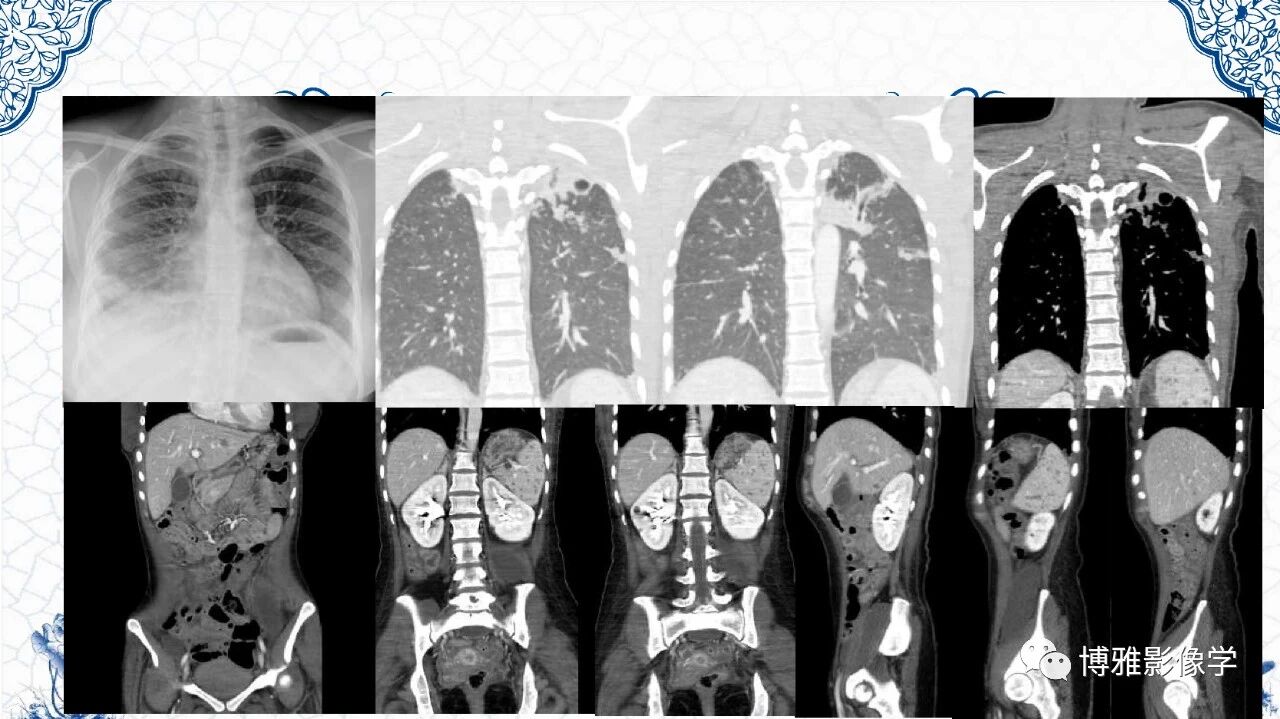

脾脏非肿瘤影像诊断